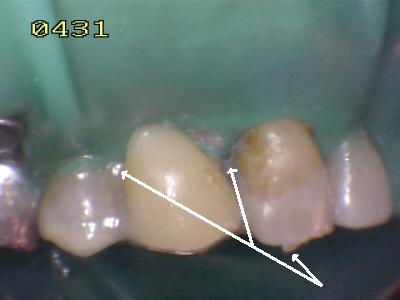

El material oscuro es una amalgama cubierta por el diseño del puuente; observe los restos de cemento adherido al esmalte dental. Caries  de esmalte y dentina en el otro pilar (flechas rojas)